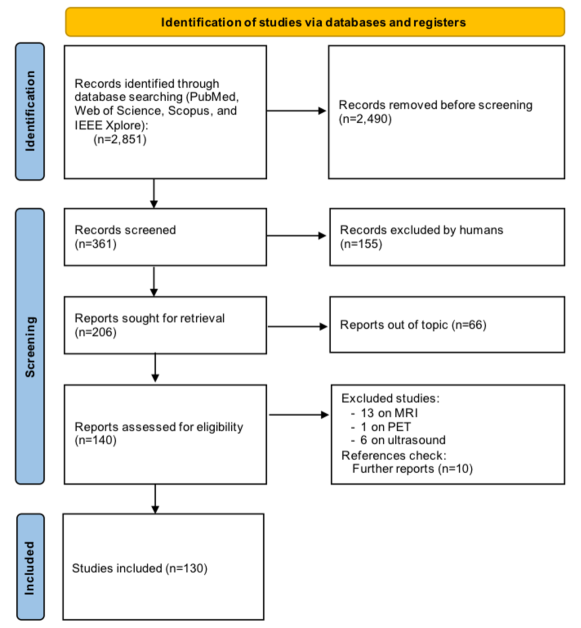

The database search retrieved 2,851 results. After title and abstract screening, the full texts of 206 reported studies were analyzed, but only 140 were found eligible for inclusion. Twenty studies using imaging acquisition other than CT (magnetic resonance imaging (MRI), positron emission tomography (PET), and ultrasound) were excluded. The list of excluded articles and the reasons for exclusion are reported in Section 2.5. Ten additional studies were retrieved after a manual check of the references. A total of 130 studies were included for full-text analysis (Fig. 2). By considering the involved countries (Fig. 3, left panel), China led the ranking with a share of 54.4%, followed by the United States (17.1%), the United Kingdom (5.3%), Canada (3.5%), and Japan (3.5%). In the majority of studies, 3D neural networks (Fig. 3, central panel) were used (51.4%), followed by 2D models (42.7%), and 2.5D (5.8%). By considering the learning type, the vast majority concern studies on supervised learning (83.8%), followed by semi-supervised learning (9.5%), and unsupervised learning (4.4%). Other types of learning (reinforcement, weakly, and continual) are reported in 2.2% of the studies (Fig. 3, right panel). Overall, there is a positive trend in the number of published articles in peer-reviewed journals, included in the present review, even though the data for the year 2023 are available until October 31st (Fig. 4). Notably, there has been a surge in the number of studies on DL for the segmentation of pancreas tumors in 2023. The 130 reviewed studies were published in high-quality peer-reviewed journals with a mean 2023 impact factor of 5.39 (latest available data according to the Web of Science). As can be seen from Fig. 5 the studies were most frequently published in prominent journals in the medical imaging domain, like Medical Imaging Analysis and IEEE Transactions on Medical Imaging, with 11 and 12 publications, respectively. Of note, there are other studies published in leading journals like IEEE Transactions on Pattern Analysis and Machine Intelligence, IEEE Transactions on Image Processing, and Nature Methods.